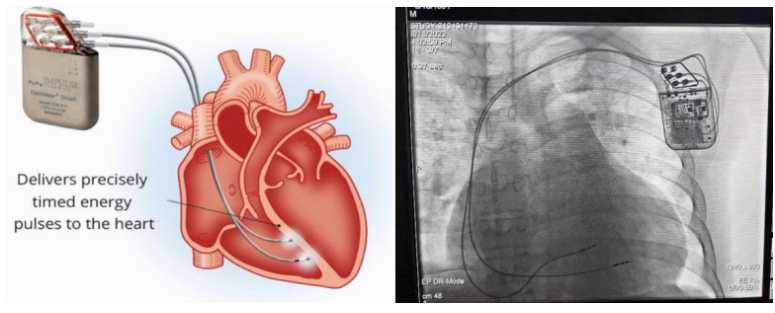

①植入式心臟復(fù)律除顫器

Implantable Cardioverter Defibrillator,ICD

植入式心臟復(fù)律除顫器是一種具有除顫功能的高級(jí)起搏器,是一種體積小、能植入患者胸部皮下組織的醫(yī)療設(shè)備。慢性心衰患者易發(fā)生室性心動(dòng)過速或心室顫動(dòng),導(dǎo)致心源性猝死(SCD)。ICD 則能在幾秒內(nèi)自動(dòng)識(shí)別并治療快速室性心律失常,通過低能量心臟轉(zhuǎn)復(fù)和高能量除顫等功能,顯著降低惡性室性心律失常引起的猝死風(fēng)險(xiǎn)??杉皶r(shí)自動(dòng)為患者轉(zhuǎn)復(fù)心律,通俗地說就是裝在體內(nèi)的自動(dòng)除顫儀。

國內(nèi)研發(fā)企業(yè):無雙醫(yī)療、邁瑞、魚躍、久心、微創(chuàng)、維偉思、麥邦等